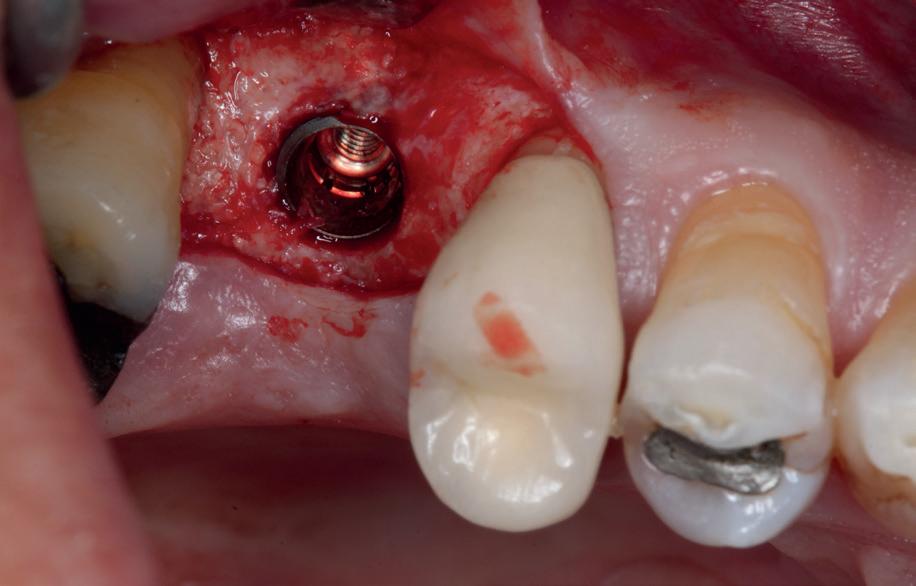

Implantologische behandelingen in het esthetische front vragen meer dan technische vaardigheid alleen. Ze vragen om overzicht, timing, vertrouwen en een team dat als vanzelf samenwerkt onder druk. Juist bij complexe casussen, waarin angst, infectie en hoge esthetische verwachtingen samenkomen, wordt zichtbaar hoe bepalend de rol van de tandartsassistent is.

Deze casus beschrijft een uitgebreide immediate implantaatbehandeling bij een patiënt die door meerdere collega’s werd geweigerd. Niet omdat de mogelijkheden ontbraken, maar omdat de complexiteit vroeg om een perfect afgestemde samenwerking. Het verhaal laat zien hoe de assistent in zo’n traject veel meer is dan een uitvoerende kracht of “mal”, maar een dynamische surgical guide die het proces mede stuurt, bewaakt en mogelijk maakt.De patiënt: wanneer alles samenkomt

Na het klinische onderzoek volgde het röntgenologisch traject. De CBCT liet precies zien wat we al vreesden: een front waarin het bot onregelmatig was, duidelijke radiolucenties rond de pijlers en een infectiegebied dat zich onder vrijwel de gehele brug had verspreid. Tegelijkertijd was er ook potentie. Net voldoende botstructuur om immediate implantaatplaatsing te overwegen, mits alles perfect gepland zou worden.